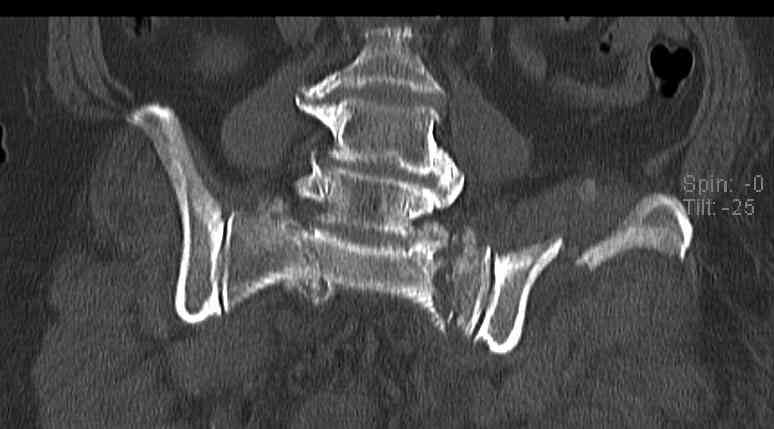

Здравствуйте уважаемые коллеги! Поступила пациентка, 61г, через 1 месяц после травмы, с двусторонним ротационно-нестабильным повреждением тазового кольца: перелом боковых масс крестца с обеих сторон, переломы лонной и седалищной костей слева, отрывные переломы передних остей левой подвздошной кости, сегментарный перелом левой подвздошной кости. Кроме того у пациентки имеется сегментарный перелом левого бедра. Перелом бедра не вызывает вопросов - планируем блокируемый остеосинтез стержнем, а вот при обсуждении тактики лечения переломов костей таза возник вопрос о необходимости синтеза остей подвздошной кости, учитывая сроки с момента травмы и наличие остеопороза могут возникнуть технические сложности. Если у кого-нибудь собственный опыт или ссылки на литературу об отдаленных результатах при не восстановлении сгибательного аппарата бедра?

Уважаемые коллеги, в продолжение обсуждения перелома костей таза с отрывами остей досылаю R-снимки (КТ и КТ с 3d реконструкцией)